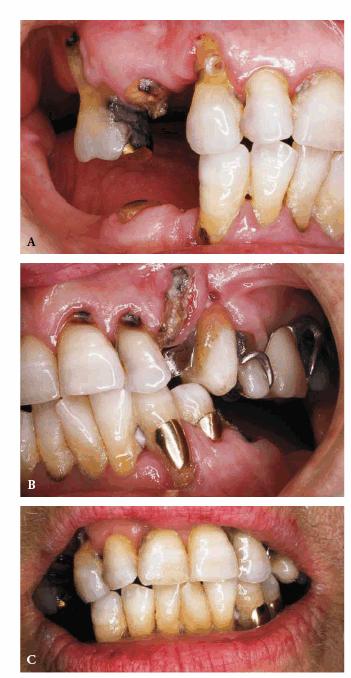

Figures 29-6A, 29-6B, 29-6C, 29-6D, and 29-6E illustrate a patient who did not care much about his

smile. The motivation for pursuing esthetic dentistry was his wife. She thought

that his smile made him look much older than his years. She encouraged him to

have esthetic dentistry by telling him that she would not kiss him until he had

his smile improved. Figures 29-6A, and 29-6D show the worn and discolored central incisors and the

crowded lower anterior incisors. Figure 29-6B shows cosmetic contouring of the lower incisors.

Figures 29-6C, and 29-6E illustrate the completed esthetic improvement following

composite resin bonding of the central incisors.

Figure 29-6A: This 65-year-old man displayed worn, discolored maxillary central incisors with a fractured anterior composite restoration on tooth #9.

Figure 29-6B: Cosmetic contouring of mandibular incisors.

Figure 29-6C: The view after composite resin bonding of his central maxillary incisors.

Figure 29-6D: This man avoided smiling to hide his worn, discolored, and fractured central incisors.

Figure 29-6E: Note how much younger and happier the patient is following his esthetic dental treatment.